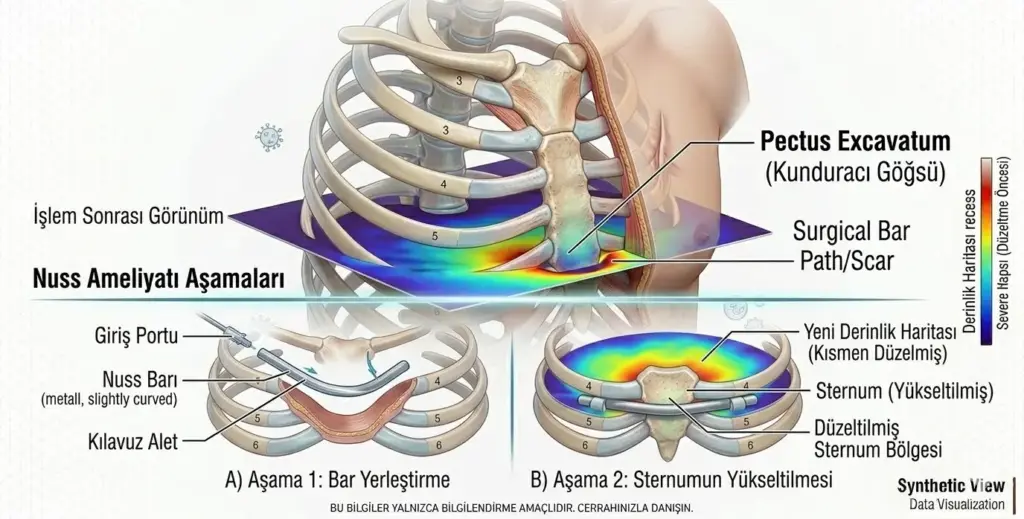

Nuss ameliyatı, kunduracı göğsü (pektus ekskavatum) tedavisinde kullanılan, minimal invaziv (kapalı) bir cerrahi yöntemdir. Geleneksel açık ameliyatlara göre...

Kunduracı göğsü, tıp literatüründeki adıyla Pektus Ekskavatum, iman tahtası olarak bilinen sternum kemiğinin omurgaya doğru çökmesiyle karakterize bir...

Nuss ameliyatı, kunduracı göğsü (pektus ekskavatum) tedavisinde kullanılan, minimal invaziv (kapalı) bir cerrahi yöntemdir. Geleneksel açık ameliyatlara göre çok daha...

Kunduracı göğsü, tıp literatüründeki adıyla Pektus Ekskavatum, iman tahtası olarak bilinen sternum kemiğinin omurgaya doğru çökmesiyle karakterize bir göğüs kafesi...